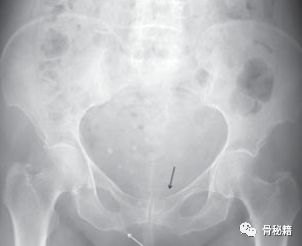

一个老年女性患者骨盆骨折,没有移位,住院后给予保守治疗后出院,出院三天后在上厕所时,腹部疼痛、尿少、心动过速、血压减低,立即入院后查体发现下腹部疼痛,压痛反跳痛,腹膜炎表现。

行CT,发现腹腔有10*10*15的血肿位于耻骨骨折旁边。